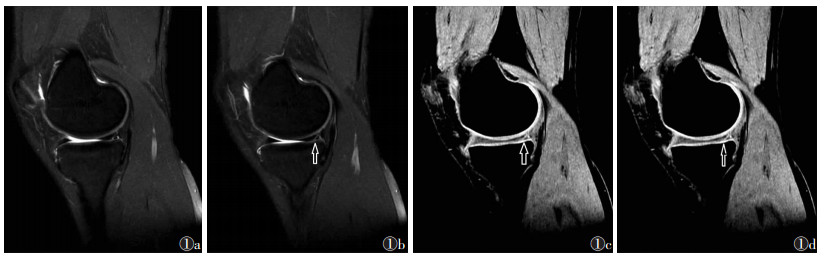

膝关节半月板损伤的典型图,见图 1

图 1 男,24岁  图 1a1b   2D-SPACE图,示半月板后角条状稍高信号,达下关节面(箭头)  图 1c1d   3D-SPACE图,示半月板后角条状高信号,达下关节面,较  图 1a1b  直观清晰(箭头)